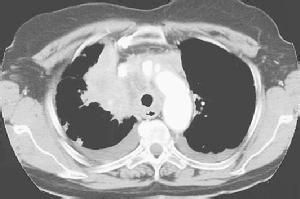

4.CT及磁共振

显示上腔静脉梗阻的部位、程度,并显示右上纵隔占位性病变。 医学百科网 | YxBaike.Com